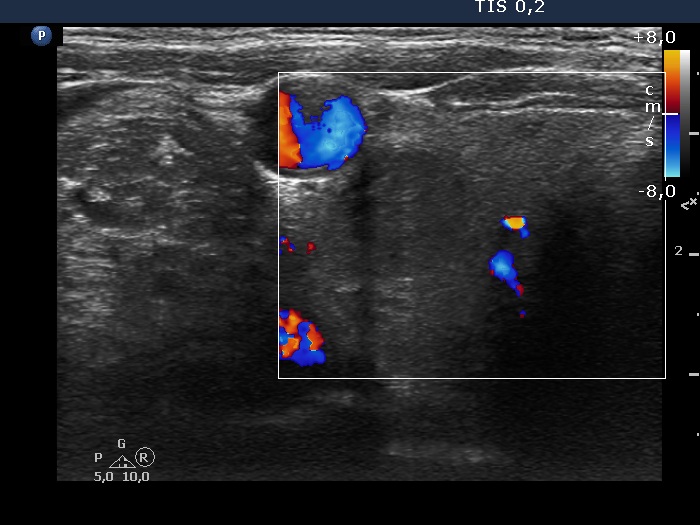

Right lobe, longitudinal scan

Right lobe, transverse scan, color Doppler mode. The lesion is avascular.